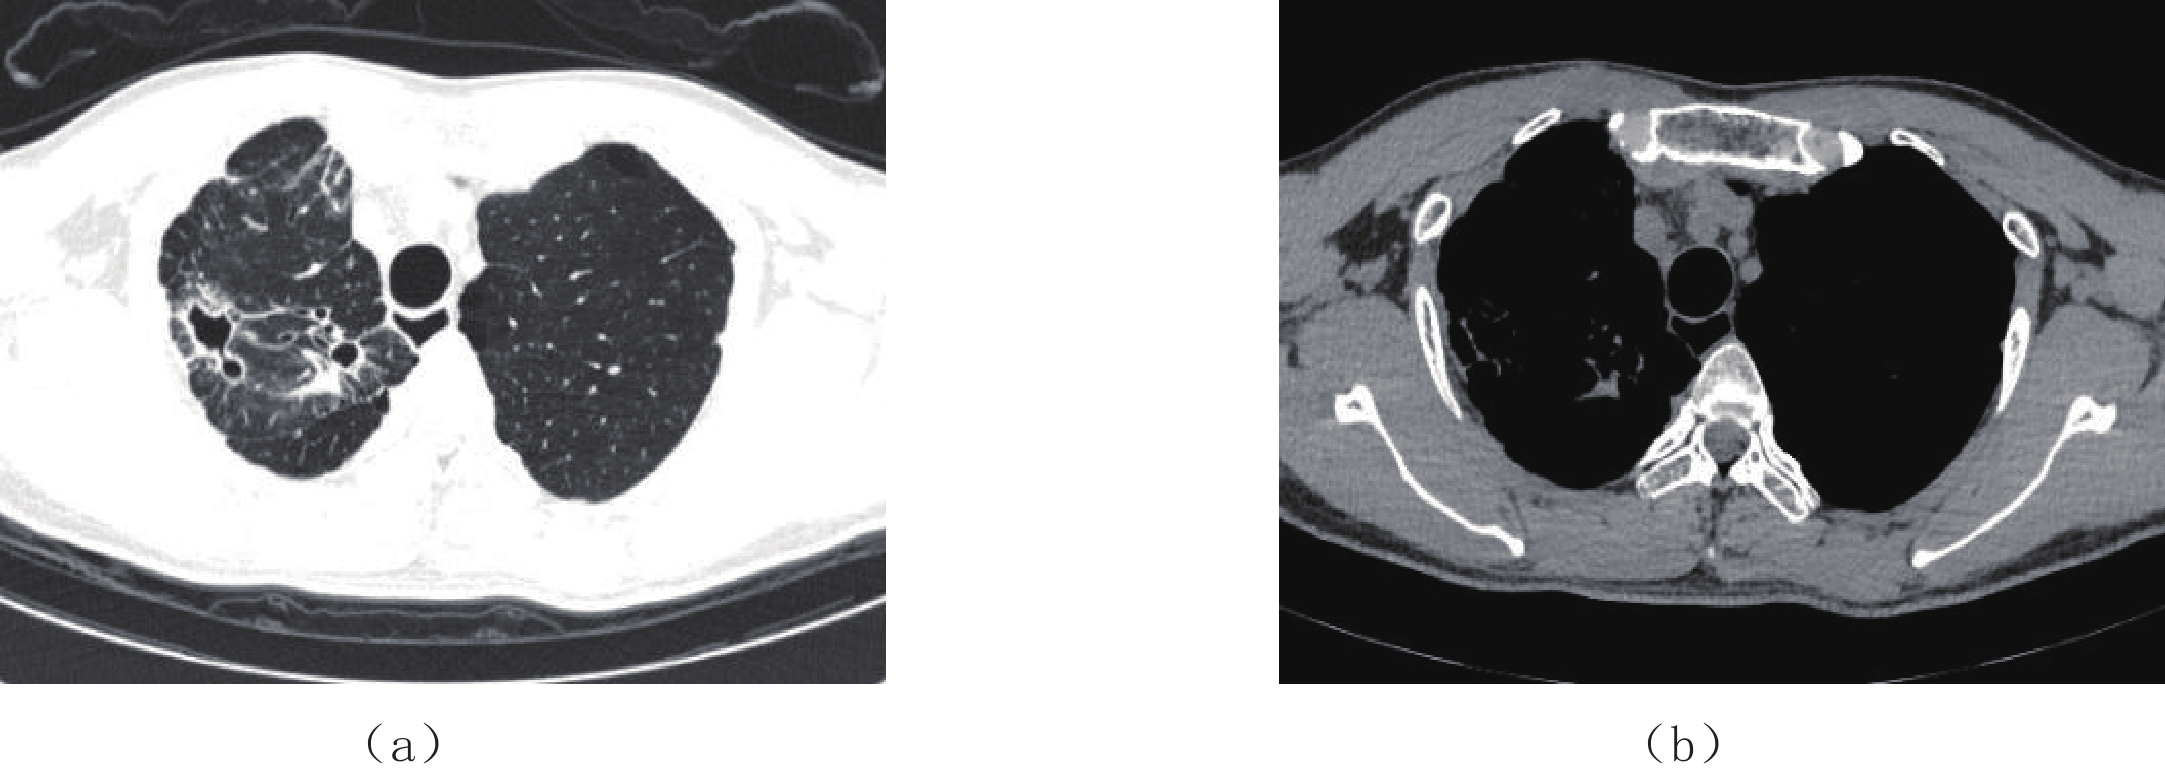

两名放射医师对两组图像主观评价一致性很好。两组图像评分结果≥3分,评分为5分居多,满足临床诊断要求;低剂量组图像主观评分与常规剂量组相比差异无统计学意义(表1、图1和图2)。